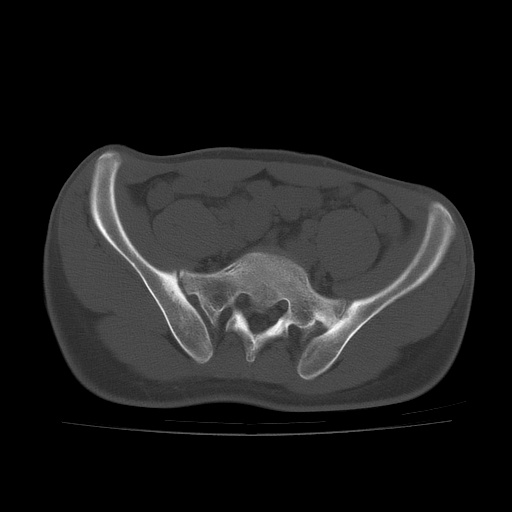

患者男性,18岁 腰腿痛1年  骶髂关节改变本人考虑强直性脊柱炎。

两侧骶髂关节骨质破坏,关节面毛糙,符合强直性脊柱炎骶髂关节改变。

两侧骶髂关节骨质破坏,关节面呈锯齿样改变关节间隙变窄,考虑强真性脊柱炎

双侧骶髂关节关节间隙变窄,边缘毛糙,关节面硬化,可见囊变!符合强直变现!

两侧骶髂关节骨质破坏以髂骨为主,间隙变窄,强直性脊柱炎